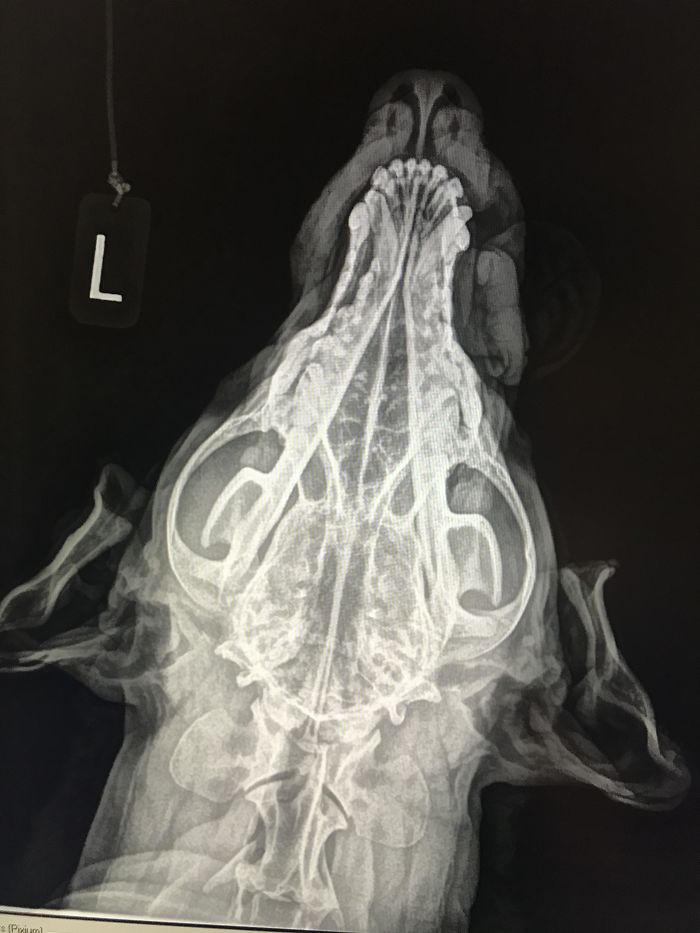

Here’s What A Canine Skull X-Ray Looks Like

When You Accidentally X-Ray Anubis. Dog Moved At Just The Right Time During An X-Ray